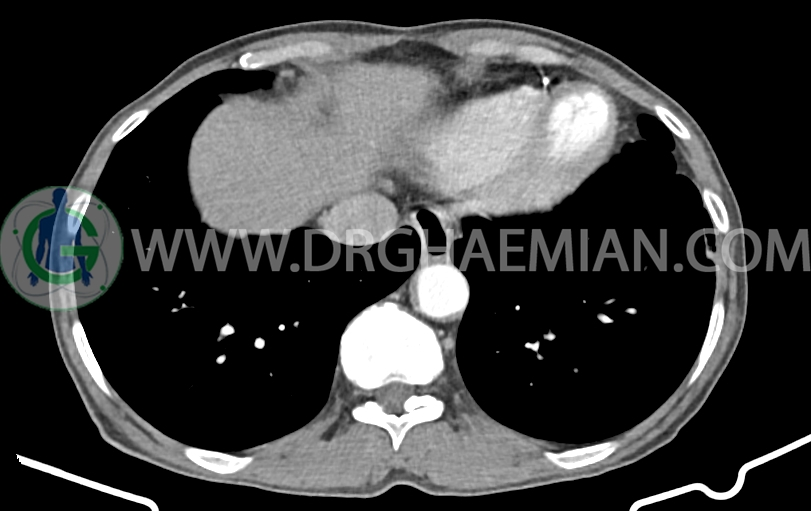

شواهدی استرنوتومی و کاردیومگالی خفیف

شواهد جراحی ویپل به صورت partial pancratectomy و کوله سیستکتومی و همچنین گاستروژژنوستومی و پانکراتیکوژژنوستومی – هپاتوژژنوستومی مشهود است .

پنوموبینی در لوب چپ کبد مشهود است.